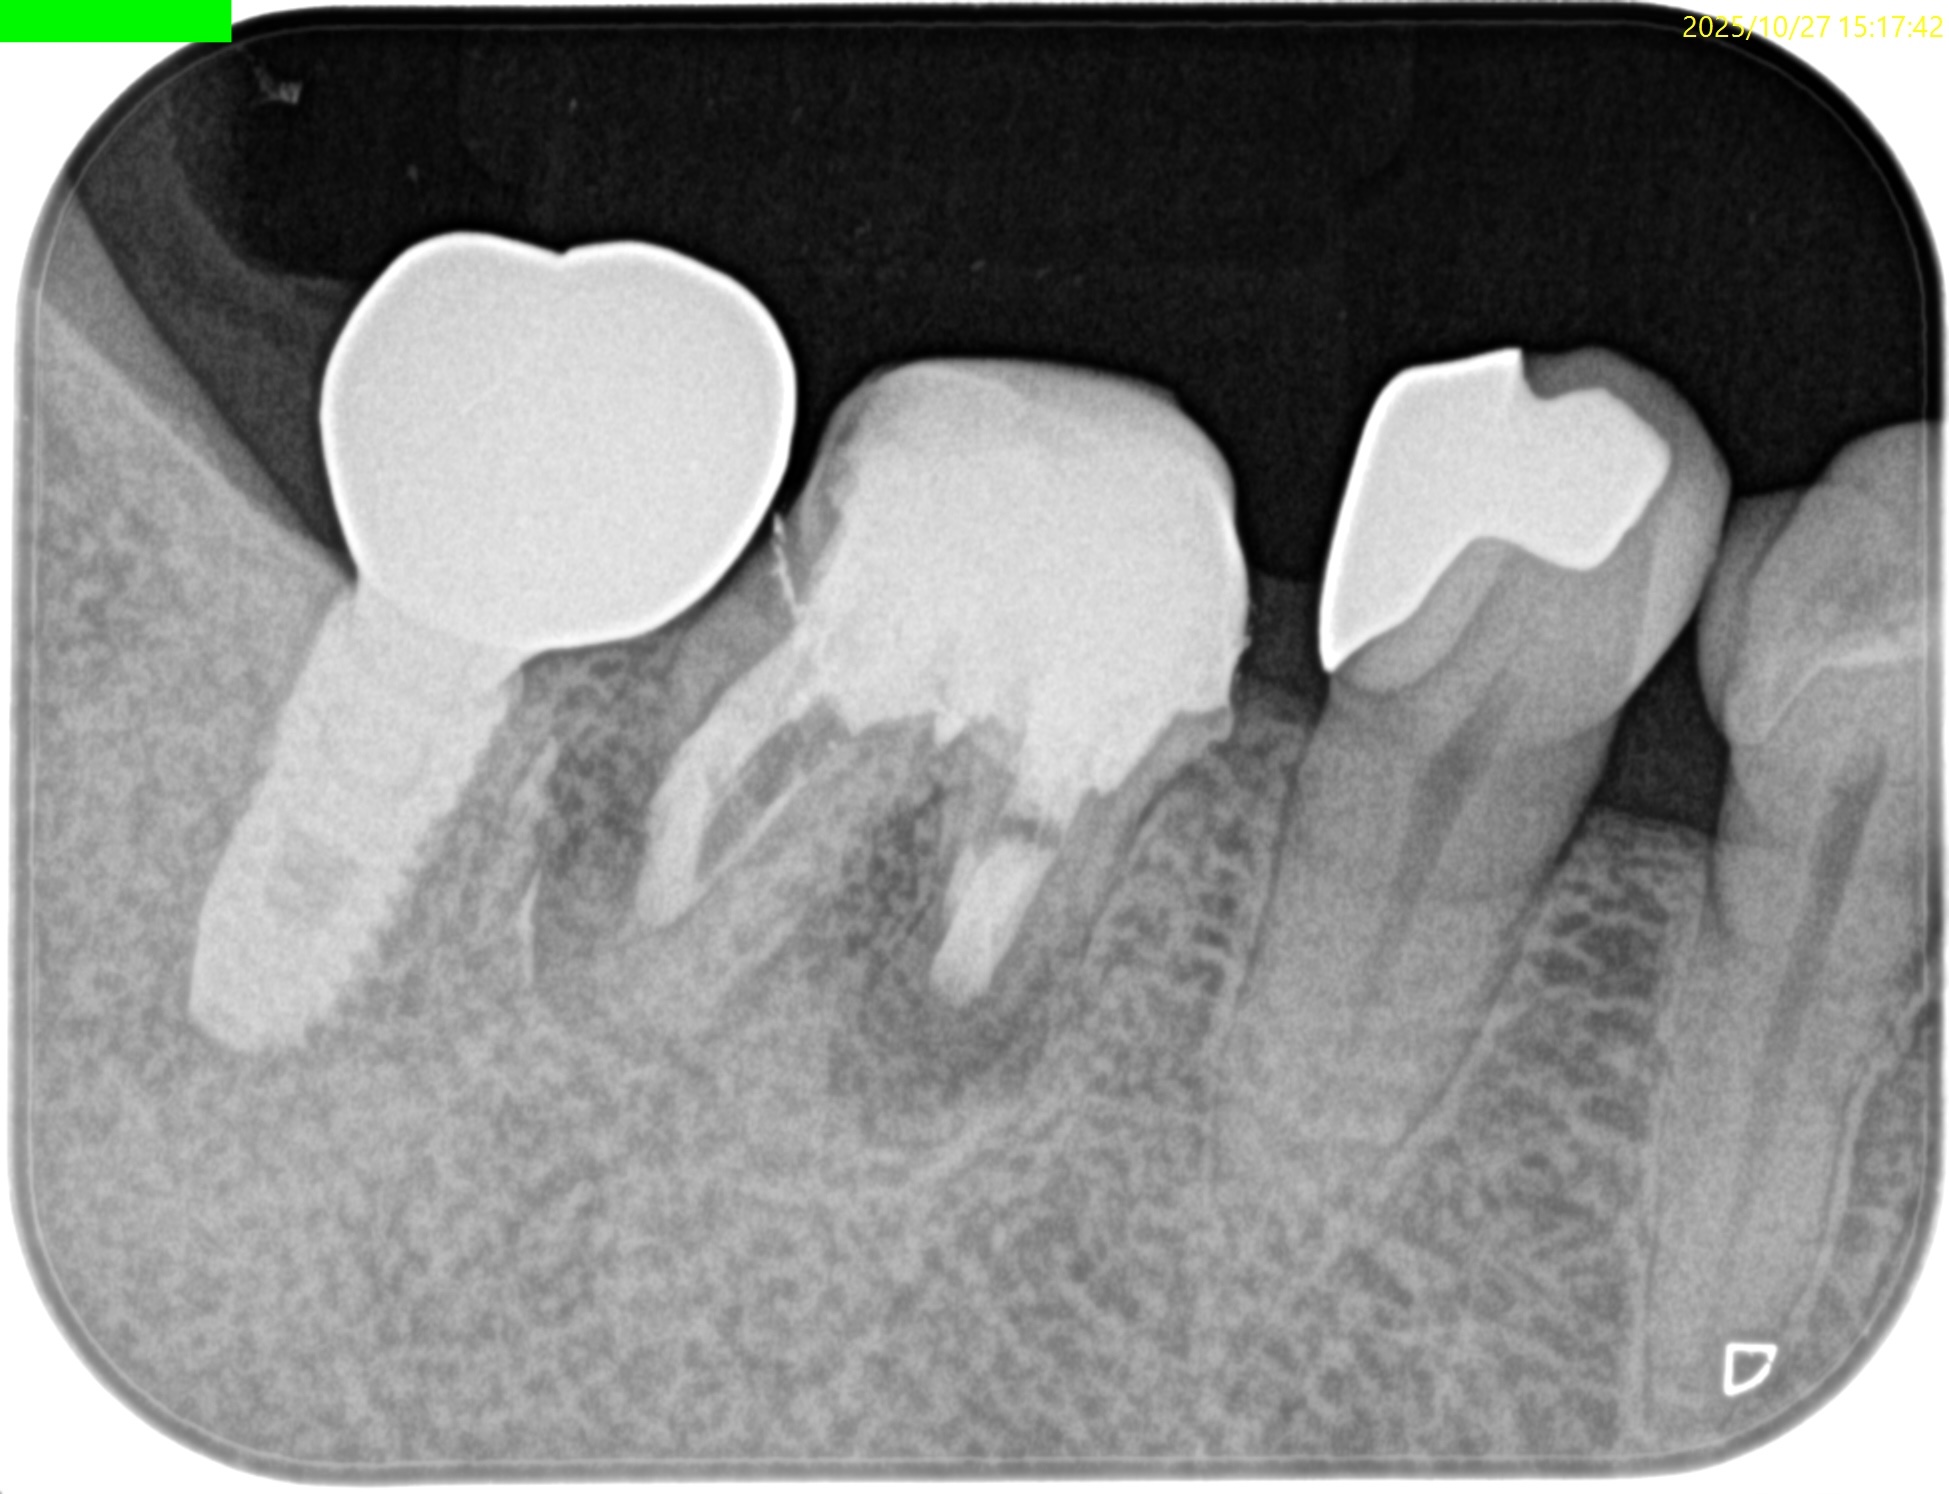

PA(2025.10.27)

近心はテーパー型、

遠心はパラレルで外れにくい感じのメタルポストコアだ。